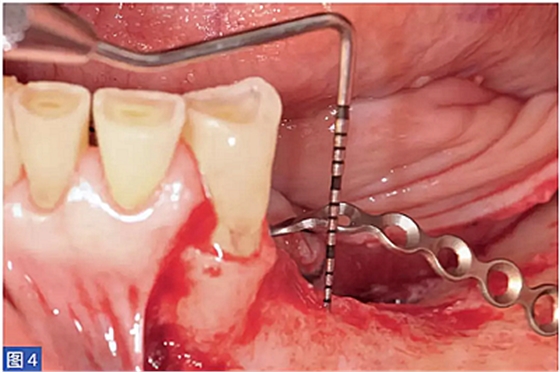

圖4:病例1. 術(shù)中內(nèi)固定鈦板。